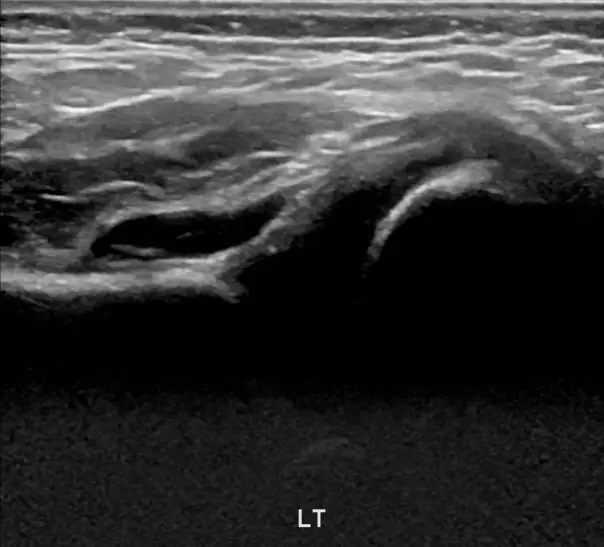

안녕하세요! 오늘은 아기 허벅지 주름이 비대칭이거나 이상하게 보일 때 꼭 체크해야 하는 내용을 알려드릴게요. 신생아나 영아의 허벅지에 자연스럽게 생기는 주름이지만, 깊이나 위치가 다르면 발달성 고관절 탈구의 신호일 수 있어요. 이 질환은 태어날 때부터 허벅지뼈가 골반에 잘 맞물리지 않는 상태로, 방치하면 걷기 어려움이나 다리 절름발이로 이어질 수 있어요. 다리 길이 차이, 다리 움직임의 이상, 걷기 시 불편함 등 증상이 있다면 빠른 검사가 필요합니다. 초음파 검사는 4주에서 6개월 사이에 가장 효과적이며, 방사선 걱정 없이 안전하게 아기 허관절 구조를 확인할 수 있어요. 조기 발견 시 간단한 치료로 정상 성장 가능하니, 아기 허벅지 주름이 이상하게 보인다면 꼭 전문가의 검진을 받아보세요. 건강한 성장과 걷기를 위해 작은 관심이 큰 차이를 만듭니다.

아기의 허벅지 주름이 비대칭이거나 다리 길이 차이, 움직임 이상이 보인다면 빠른 검진이 중요합니다. 초음파 검사는 안전하고 정확한 방법으로, 조기 치료를 통해 정상적인 성장과 걷기를 기대할 수 있어요. 부모님들이 작은 신호도 놓치지 말고 정기 검진을 챙기시는 게 좋아요.